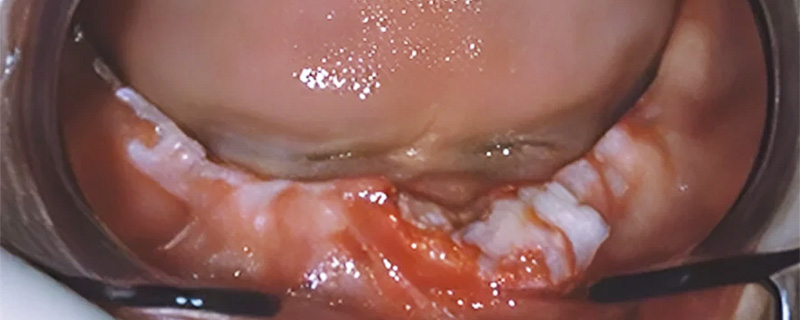

Fig. 02 : cancer invasif de la voûte palatine.